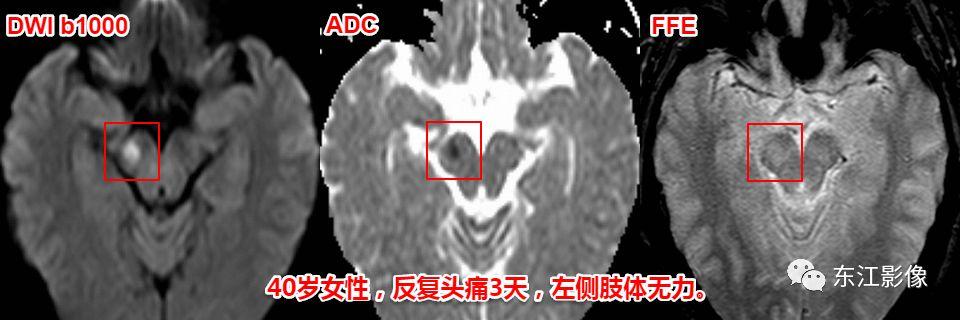

中脑急性梗死,与扩大的血管周围间隙比较。